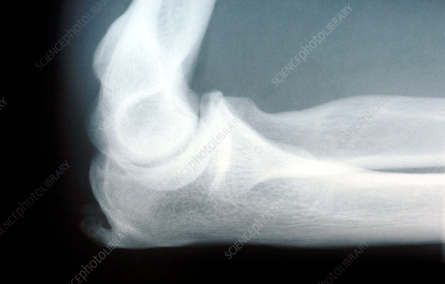

X-ray상 주두 부위의 골극 소견